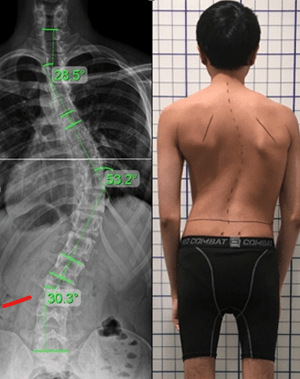

برای اندازهگیری شدت اسکولیوز زاویه کاب (Cobb Angle) را محاسبه میکنند. در این روش دو خط از شروع و پایان انحراف با همان زاویه میکشند و سپس آن دو خط را بهوسیله دو خط قائم دیگر به یکدیگر وصل میکنند. زاویهای که میان خطوط جدید شکل میگیرد، نشاندهنده میزان شدت انحراف است. در موارد بسیار خفیف، به دلیل زاویه کم، حتی ممکن است که تغییرات ظاهری در کمر و ستون فقرات مشاهده نشود، اما در موارد شدید علائمی مانند عدم تقارن شانهها یا لگن و همچنین برجستگی کتف در یک سمت مشاهده میشود.

- تصویربرداری

پس از اینکه اسکولیوز تشخیص داده شد، پزشک برای اندازهگیری دقیق میزان انحراف ستون فقرات درخواست تصویربرداری میکند. تصاویر رادیوگرافی به وضوح انحراف ستون فقرات را نمایش میدهد. پزشک از این طریق میتواند بررسی کند که ستون فقرات چقدر منحرف شده است. این تصویر معمولاً از دو جهت گرفته میشود: یکی از جلو (پروب به جلو) و دیگری از کنار (پروب به پهلو) تا انحراف در هر دو بعد مورد بررسی قرار گیرد.

- بررسی میزان انحراف

پس از گرفتن تصویر، پزشک میزان انحراف ستون فقرات را با دقت اندازهگیری میکند. این اندازهگیریها معمولاً با استفاده از خطوط مرجع انجام میشود که پزشک روی عکس رادیوگرافی رسم میکند. این خطوط به طور خاص در نقاطی از ستون فقرات که انحراف وجود دارد، کشیده میشوند. پزشک این خطوط را بررسی میکند تا زاویهای که انحراف ایجاد کرده را اندازهگیری کرده و میزان شدت انحراف را تعیین کند.

شدت اسکولیوز به میزان انحنا و پیچش ستون فقرات بستگی دارد. بهطور کلی، اسکولیوز به سه دسته تقسیم میشود: خفیف (کمتر از ۲۵ درجه)، متوسط (بین ۲۵ تا ۴۵ درجه)، و شدید (بیش از ۴۵ درجه). در درجات خفیف، معمولاً علائم کم و درمانهای غیرجراحی مانند فیزیوتراپی و بریس مؤثر هستند. در درجات متوسط، نیاز به مراقبتهای بیشتر و گاهی استفاده از بریس وجود دارد. در درجات شدید، جراحی معمولاً پیشنهاد میشود، زیرا ممکن است مشکلاتی چون درد مزمن، مشکلات تنفسی یا آسیب به اندامهای داخلی پیش آید.